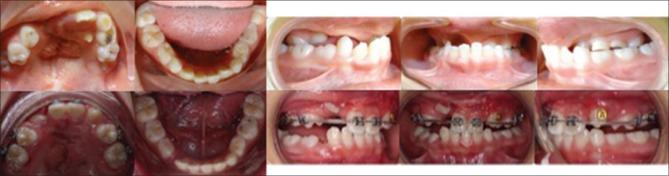

The patient presented in this paper was an Asian female with CLP aged 13 years and 6 months. She presented with severe midfacial deficiency with a Class III dental malocclusion with a negative overjet and concave facial profile. Cone-beam computed tomography images were recorded preoperatively and the operation performed involved a high Le Fort I osteotomy. The appliance fabricated was banded to upper first molars used for anchorage of the RED system. Distraction of the maxilla was initiated after 7-day latency period.

Postoperative cephalometric analysis showed maxillary advancement anteriorly and superiorly, the total distraction treatment period was 10 days. The maxillary advancement was 10.5 mm and the SNA angle increased from 67.5° to 77.9°. Furthermore, the ANB angle changed from -9.8° to 1.6° and the occlusion changed from Class III to Class I. The profile of the face changed from concave to convex and a much better esthetic result was achieved.

结果

术后头影测量分析显示上颌骨向前上方移动,总牵张治疗期为10天。上颌骨前移10.5mm,SNA角从67.5°增加到77.9°。此外,ANB角从-9.8°变为1.6°,咬合关系从III类变为I类。面部轮廓从凹陷变为凸起,美学效果更佳。